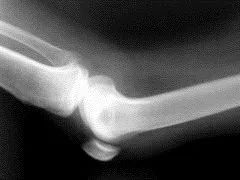

另外,骨骼的愈合能力、愈合程度等都需要X线片提供有效信息,因此定期拍片也不可少。